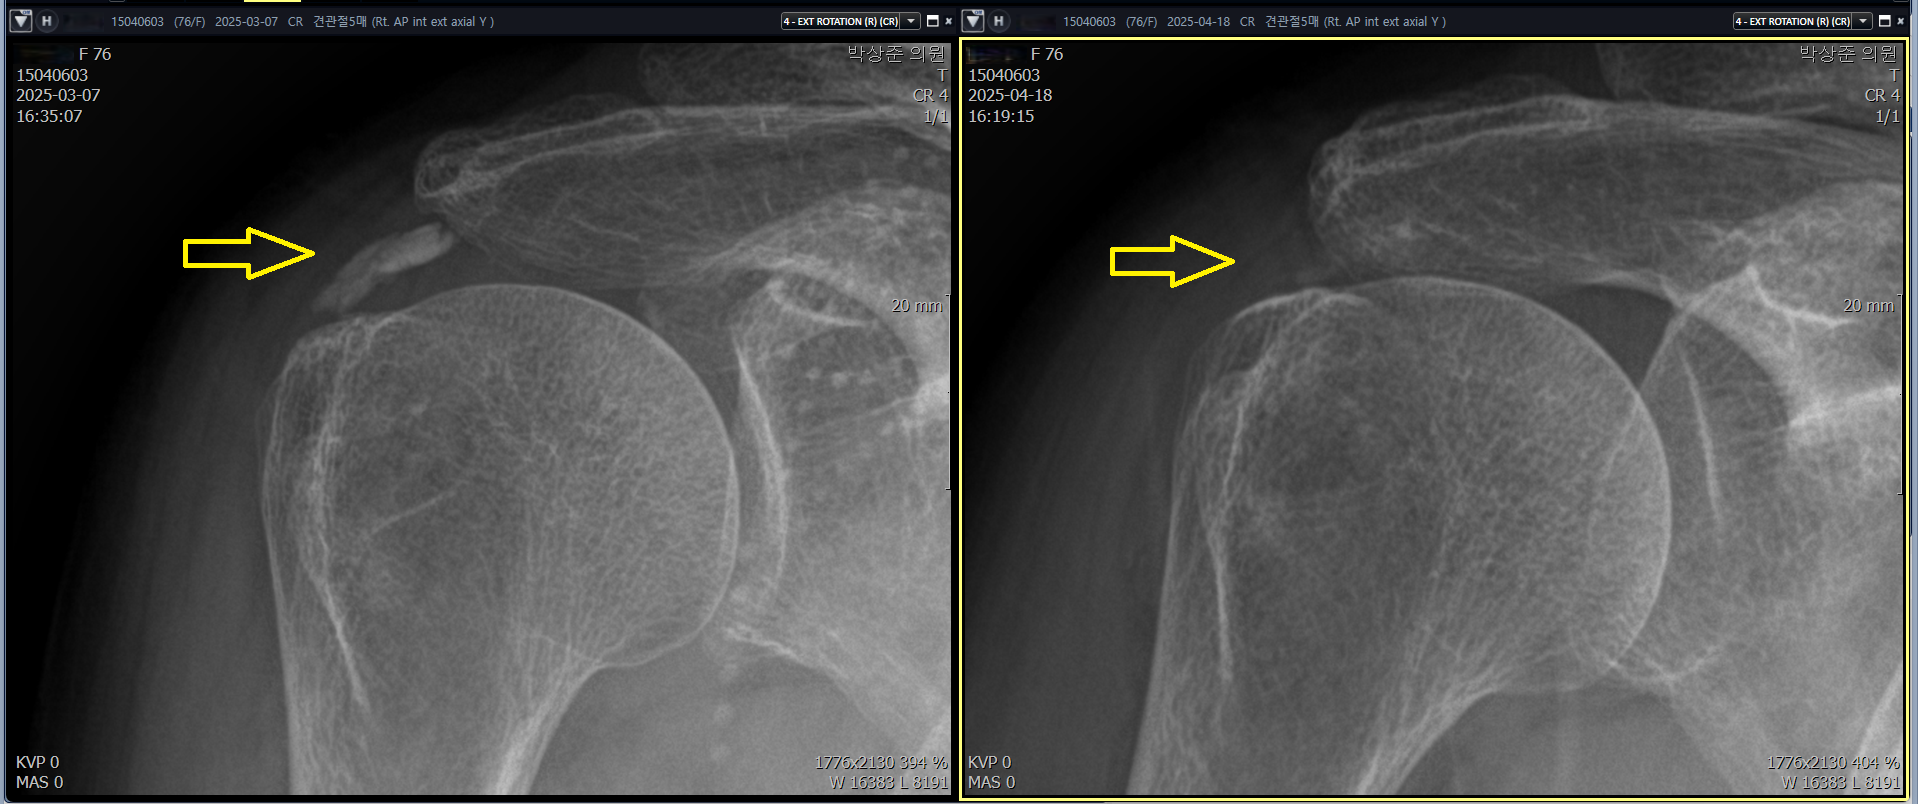

당산 정형외과, 당산역 정형외과, 영등포 정형외과안녕하세요 오늘은 충격파 치료만으로 해결이 되지 않던 석회성 건염 환지의 치료 사례를 보여드리겠습니다. 얼마전 진료실에 연세가 70이 넘으신 어르신이 오셨습니다.나 : 어르신 어디가 아파서 오셨어요? 환자 : 어깨가 아파요 나 : 아픈지 얼마나 되셨어요? 환자 : 6개월 정도는 된거 같네요. 나 : 그동안 치료 안받으셨어요? 환자 : 치료했죠. 다른 병원에서 어깨에 석회가 끼었다고 해서 그동안 계속 치료 받았는데도 계속 아프네요 나 : 아 그래요? 무슨 치료를 받으셨어요? 환자 : 석회를 깨트리는 충격파 치료라고 해서 받았어요. 거의 10번은 받은거 같은데...석회성 건염(석회화 건염)을 진단받고 체외 충격파 치료만 무려 10회 이상 받았다는 환자, 팔을 ..